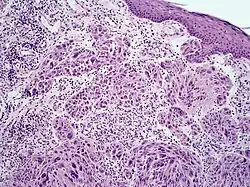

Melanoma with features of a Spitz nevus

Melanoma with features of a Spitz nevus, also known as a Spitzoid melanoma, is a cutaneous condition characterized histologically with tissue similar to a spitz nevus and with overall symmetry and a dermal nodule of epithelioid melanocytes that do not mature with progressively deeper dermal extension.[1]